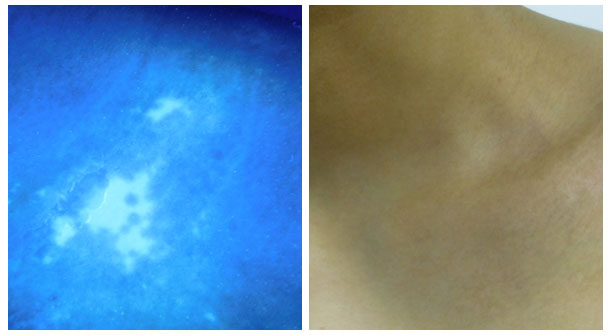

接诊浩浩的是我院第七科室主任——高霞主任。高主任为浩浩做了系统检查如伍德灯检查、皮肤ct检测等。高主任通过伍德灯检查发现患者锁骨、胸部、腹部、肢端部位、腰部、双胯等多部位存在白斑,随后在多项白斑检测的结果下诊断患者浩浩的病情为进展期白癜风。

同时了解到浩浩是牛皮癣恢复后脱屑部位皮肤变白从而诱发的白癜风,且无家族史。通过观察患者的白斑属于全身散发性白斑,部分白斑周边边界不清晰,面积大小不等,形状不规则,呈纯白色,表面光滑,无皮屑,部分白斑间可见色素岛,白斑处感觉无异常,无明显毛发变白。